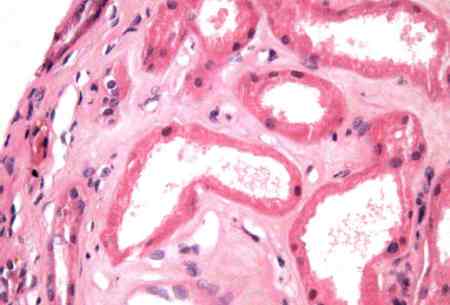

- renal biopsy:

demonstrates onion-skinned vascular lesions; may have evidence of thrombotic microangiopathy